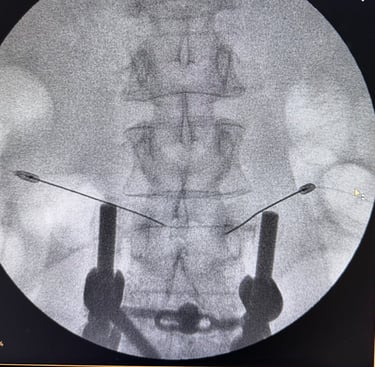

Neurocirurgia endovascular

Tratamento de doenças vasculares do cérebro e da medula espinhal por meio de técnicas minimamente invasivas — realizadas por cateteres, sem a necessidade de incisões cirúrgicas.